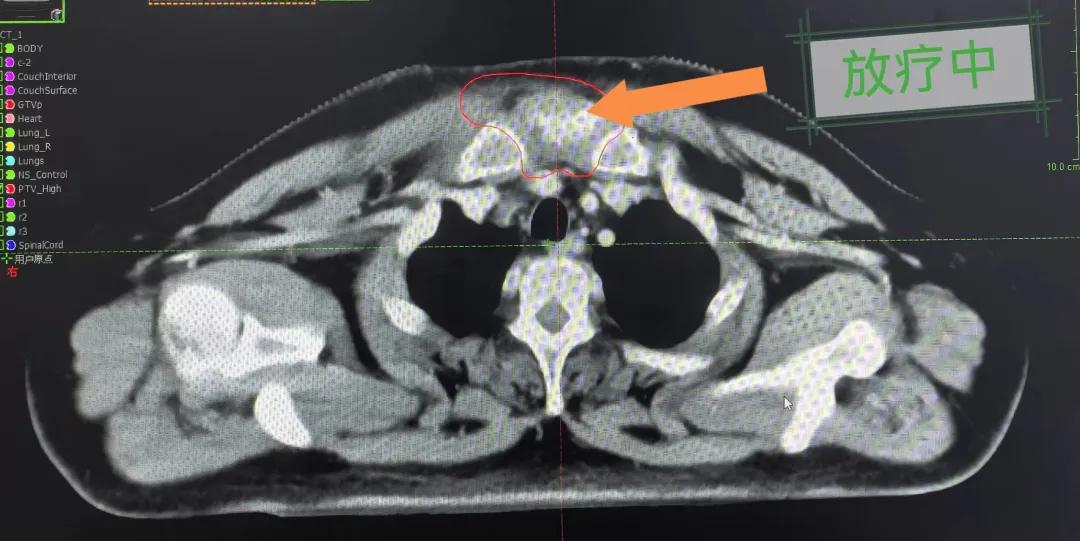

隨后,趙亮主任帶領(lǐng)放療團(tuán)隊以最快的速度完成了患者的放射治療計劃,在保證放療精準(zhǔn)打擊腫瘤的同時,利用先進(jìn)的三維立體精確放療技術(shù),最大限度的避免心臟、肺部的損傷發(fā)生,整體治療精準(zhǔn)度達(dá)到1mm以內(nèi)。經(jīng)過10次的放射治療后,患者疼痛已明顯減輕,胸部腫物肉眼可見的縮小,患者及家屬臉上終于露出久違的笑臉。

治療期間,患者沒有出現(xiàn)明顯不適,治療結(jié)束后,患者胸壁腫物由最初8cm縮小至約1cm,后患者至外科行手術(shù)治療。